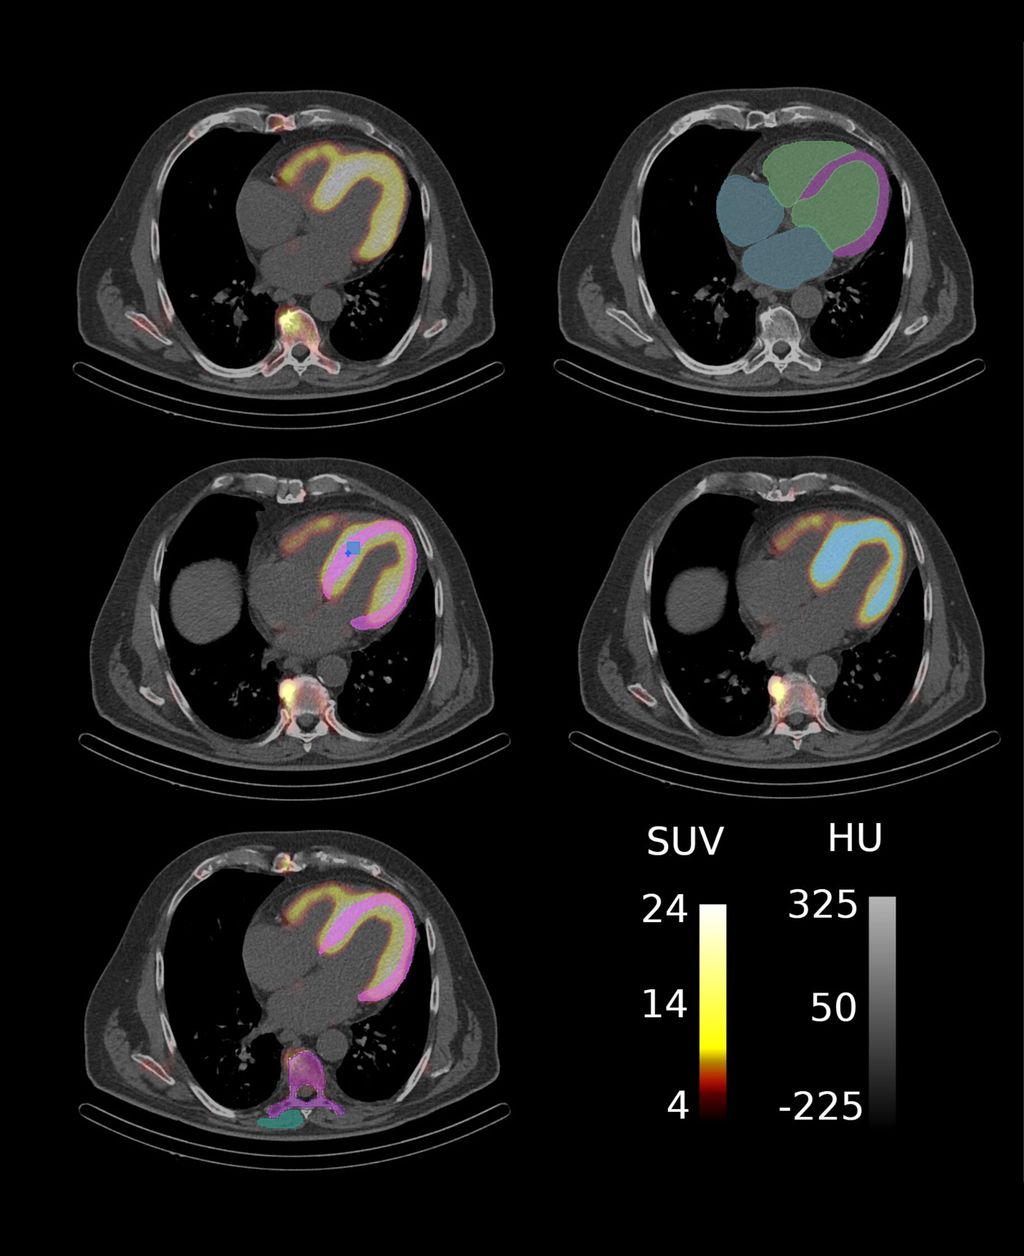

Im Rahmen einer explorativen bildgebenden Studie der Klinischen Abteilung für Kardiologie in Kooperation mit der Klinischen Abteilung für Nuklearmedizin der Medizinischen Universität Wien wurde der Einfluss amyloidspezifischer Therapien auf SPECT/CT-basierte Marker untersucht (Abb. 2), die myokardiale Amyloidablagerungen widerspiegeln. Die KI-gestützte Segmentierung der kardialen Strukturen ermöglicht eine umfassende Quantifizierung der Amyloidablagerungen im Myokard und können als potenzielle nichtinvasive bildgebende Biomarker zur Überwachung der therapeutischen Wirksamkeit bei Patient:innen mit ATTR-CM dienen (Abb. 3).

Die Studienkohorte umfasste 45 Patient:innen mit ATTR-CM, die eine amyloidspezifische Therapie, wie TTR-Stabilisatoren (Tafamidis) oder TTR-Silencer (Patisiran, Inotersen), erhielten und sich sowohl vor Therapiebeginn als auch nach neun Monaten im Rahmen eines Follow-ups einer SPECT/CT-Bildgebung unterzogen. Die KI-gestützte Segmentierung der kardialen Strukturen erfolgte mithilfe eines Deep-Learning-Modells, das die automatisierte Extraktion von 23 quantitativen Markern ermöglichte, darunter Intensitäts- und Volumenmarker des Tracer-Uptakes sowie der Retentionsindex über verschiedene kardiale Substrukturen. Darüber hinaus wurden funktionelle Parameter – einschließlich klinischer und laborchemischer Variablen – sowie klinische Endpunkte hinsichtlich ihrer Assoziation mit Veränderungen der SPECT/CT-Marker vor und nach der Behandlung untersucht.

Abb. 2: ATTR-CM Patient mit Segmentierungsmasken für myokardbasierte Marker: (a) SPECT/CT Aufnahme, (b) CT-Aufnahme mit Basis-Segmentierungen, (c) Segmentierung zur Extraktion klassischer SUV-Parameter wobei SUVpeak in Hellblau und SUVmax in Dunkelblau dargestellt ist, (d) Segmentierung des Amyloid-assoziierten Volumens und (e) Segmentierungen für den Retentionsindex. (Quelle: eigene Anfertigung)